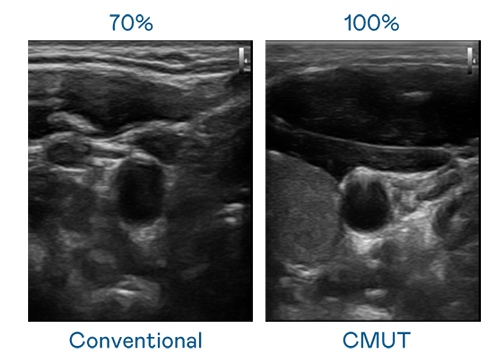

CMUT 技术是一种用电容式微机电元件来产生超音波讯号的技术。与传统 PZT 压电式技术相比,CMUT 频宽增加 30%,更宽频的超音波讯号让影像解析度大幅提升,是实现高影像品质医疗超音波扫描、促进精准医疗发展的关键技术。

大频宽带来超清晰影像

超音波影像的解析度高低,首先取决于探头能发出的讯号频宽。抖圈 CMUT 可提供高清晰的超音波讯号,提供高频宽、高灵敏度、影像纹理细节更高的超音波影像,协助医护人员缩短影像判读时间及利用精准的医疗影像进行诊断。